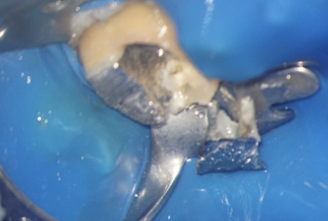

Pivotul de metal este voluminos și cimentat în două dintre canale și în perforație, așa că trebuie segmentat pentru a fi îndepărtat (Fig. 4.12.5, Fig. 4.12.6, Fig. 4.12.7).

După îndepărtarea unui segment din pivot, vedem cavitatea artificială care traversează grosimea dintelui, până în țesutul de susținere (Fig. 4.12.8). În țesutul de susținere se observă un material albastru, gumos. Este cel mai probabil un material din clasa silicaților, folosit pentru amprentarea spațiului din interiorul dintelui pentru confecționarea pivotului metalic (Fig. 4.12.9). Reușim să îndepărtăm o parte a acestui material și închidem perforația folosind un ciment bioceramic (MTA) (Fig.4.12.10, Fig. 4.12.11).